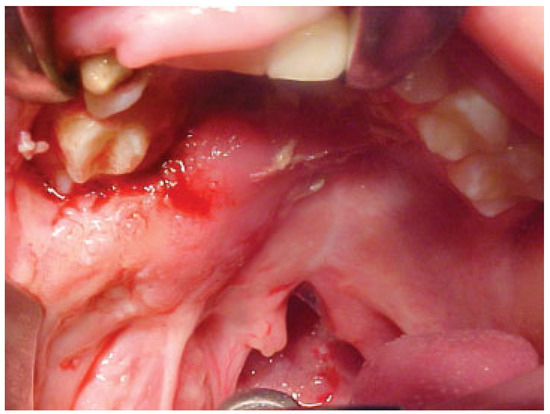

Case 9

A 7-year-old boy with a history of bilateral cleft lip and palate presented with an anterior fistula measuring 40 × 28 mm after palatal surgery (Figure 11). The fistula was closed with a left anteriorly based NAMMC flap (Figure 12, Figure 13 and Figure 14).

Figure 9. Severe fistula located on the hard palate after primary palatoplasty in an 8-year-old patient with bilateral cleft lip and palate.

Cmtr 05 00022 g009

Figure 10. Postoperative (2 weeks) view of the patient in Figure 9 after closure of the fistula using an anteriorly based nasal artery musculomucosal cutaneous flap.